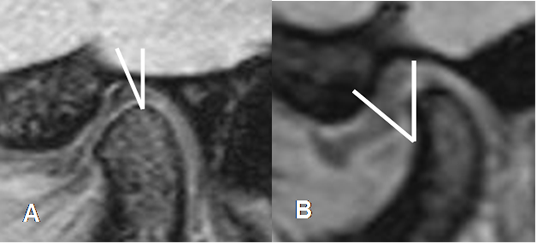

No confundir el disco desplazado, con la inserción del músculo pterigoideo lateral en el cóndilo mandibular, por debajo de la ubicación del menisco. (2). (Fig 12).

Fig 12. Músculo Pterigoideo normal.

RM sagital oblicua en GE. Músculo normal, por debajo de la banda anterior del disco.